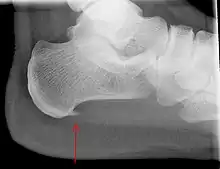

An incidental finding associated with this condition is a heel spur, a small bony calcification on the calcaneus (heel bone), which can be found in up to 50% of those with plantar fasciitis.[6] In such cases, it is the underlying plantar fasciitis that produces the heel pain, and not the spur itself.[13] The condition is responsible for the creation of the spur though the clinical significance of heel spurs in plantar fasciitis remains unclear.[12]

Medical imaging is not routinely needed. It is expensive and does not typically change how plantar fasciitis is managed.[15] When the diagnosis is not clinically apparent, lateral view X-rays of the ankle are the recommended imaging modality to assess for other causes of heel pain, such as stress fractures or bone spur development.[7]

The plantar fascia has three fascicles-the central fascicle being the thickest at 4 mm, the lateral fascicle at 2 mm, and the medial less than a millimeter thick.[19] In theory, plantar fasciitis becomes more likely as the plantar fascia's thickness at the calcaneal insertion increases. A thickness of more than 4.5 mm ultrasound and 4 mm on MRI are useful for diagnosis.[20] Other imaging findings, such as thickening of the plantar aponeurosis, are nonspecific and have limited usefulness in diagnosing plantar fasciitis.[13]

A determination about a diagnosis of plantar fasciitis can usually be made based on a person's medical history and physical examination.[22] When a physician suspects a fracture, infection, or some other serious underlying condition, they may order an X-ray to investigate.[22] X-rays are unnecessary to screen for plantar fasciitis for people who stand or walk a lot at work unless imaging is otherwise indicated.[22]